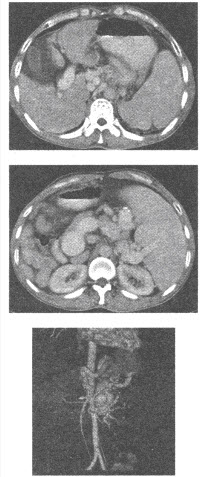

男,38岁。CT增强扫描示肝脏体积缩小,肝表面欠光整;肝裂增宽,肝叶比例失调,尾叶较大。肝实质密度不均。脾大。脾门及贲门周围可见团状软组织影,静脉期呈高密度,脾门及贲门周围团状软组织影应考虑为()

正确答案:C